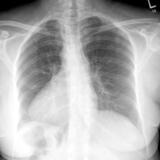

Bronch Cyst 1 PA

Date: 05/11/2004

Views: 6136